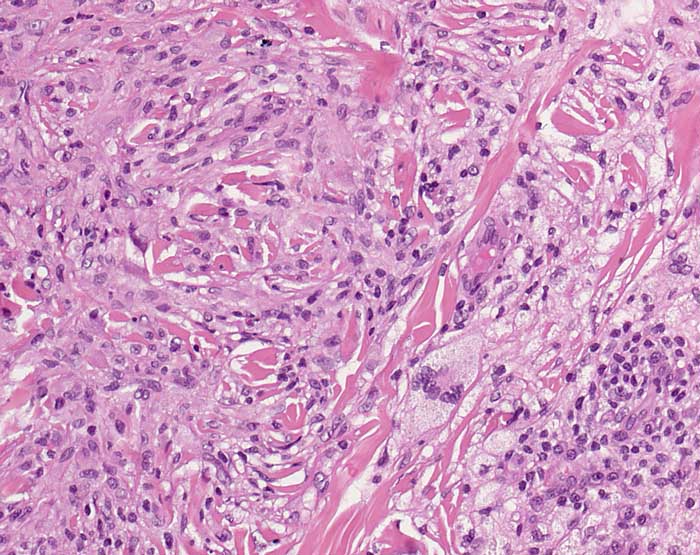

Nekrobiotisches Xanthogranulom

Systemerkrankung/Immunpathologie

Haut, Kopf

Diffuses Infiltrat von Histiozyten, Schaumzellen und Touton-Riesenzelle.

Paraproteinämie bei multiplem Myelom. Gelbliche Plaques an der Stirn und im Schulterbereich.

Histologie

200